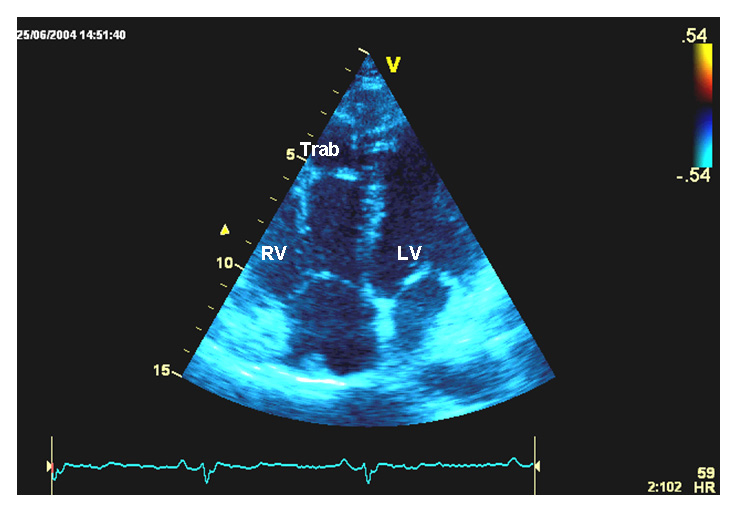

At the age of thirteen, the clinical examination was consistent with curly and woolly blond hair with high frontal hairline. Although shape and dental enamel of teeth were normal, she had dental agenesis with missing teeth numbers 14, 15, 17, 25, 27, 35, 37, 45 and 47. Furthermore she exhibited slight plantar keratosis, toe intertrigo and minimal palmar keratosis. Nail examination revealed bilateral leuconychia of third and fourth toe whereas finger nails were normal. While she had no cardiac symptoms, her resting electrocardiogram showed regular sinus rhythm, left hemi bundle-branch block and an epsilon wave. Her Holter ECG recordings showed frequent ventricular premature beats. Echocardiographic findings were consistent with severe RV dilatation and slight LV enlargement from the apical-4 chamber view (fig. 2A, B). At 22 years, an ICD was implanted following three episodes of syncope.

Figure 2

Transthoracic echocardiography, and genetic screening of case 2.

B  Apical four chamber view. Right ventricular trabeculations are visible at the free wall level.

RV = right ventricle; Trab = trabeculations; LV = left ventricle.